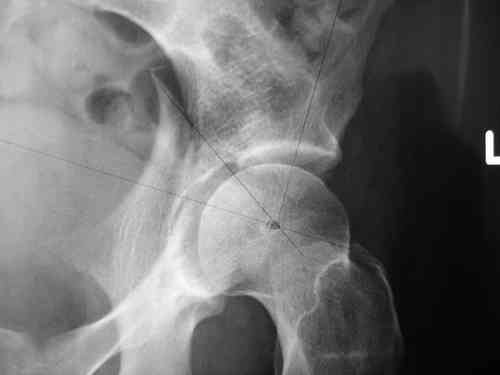

прилагаю пример с такой же давностью травмы, репонировали аппаратом

> в аппарате или одномоментно открыто. Лично я склоняюсь к аппаратному лечению на первом этапе.